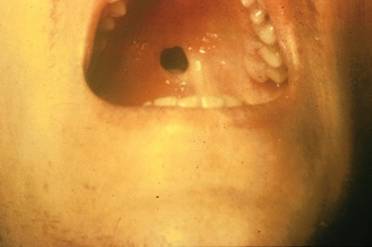

Perforazione del palato

Si può avere una perforazione tardiva del palato. Altre manifestazioni sono neurologiche e a carico degli organi addominali.